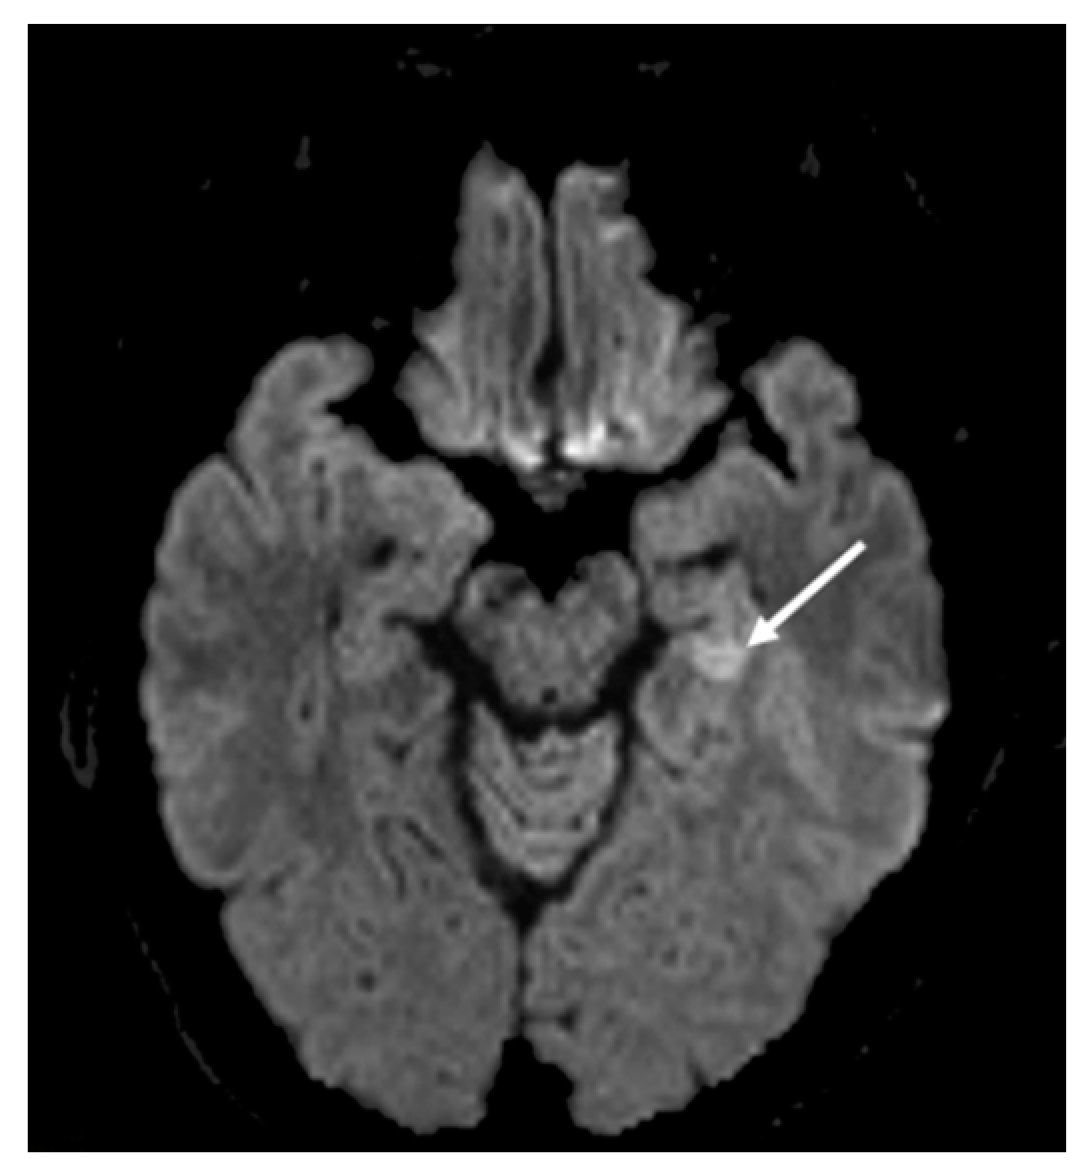

1. Patient Case History and Clinical Presentation

2. Hospital Examination and Laboratory Findings